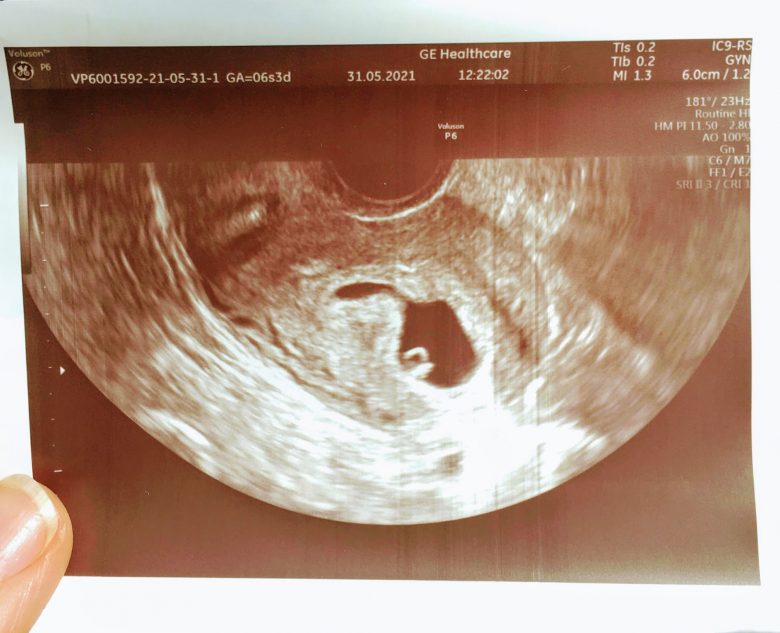

Both my husband and I were cautiously happy. We did not want to get our hopes up before confirming that it was a viable pregnancy. Our thinking was: first make sure it was fixed in the right place; then make it through the first trimester; then wait for the pre-natal genetic screening to come back ok. Only then would we take a breath and allow ourselves to truly enjoy it.

What followed were two weeks of feeling pregnant in a completely different way than the first time. Small, but constant discomfort was the norm. Tiredness. Anxiety. Imagining all the different ways in which things could go wrong. Finally, a healthy baby girl is growing inside my tummy, with a family of three waiting to meet her when she is strong enough and ready to come out.